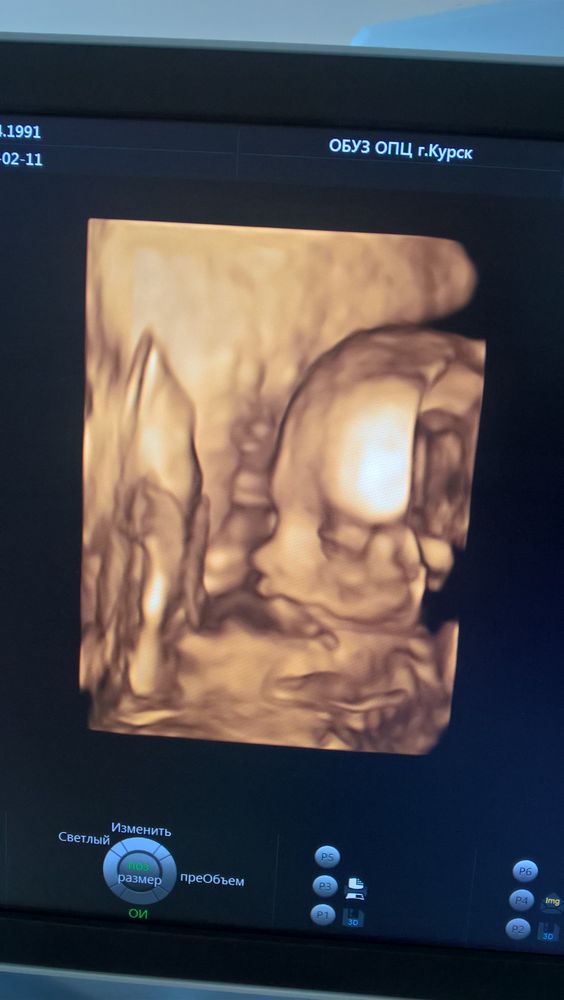

Почти в 32 недели.